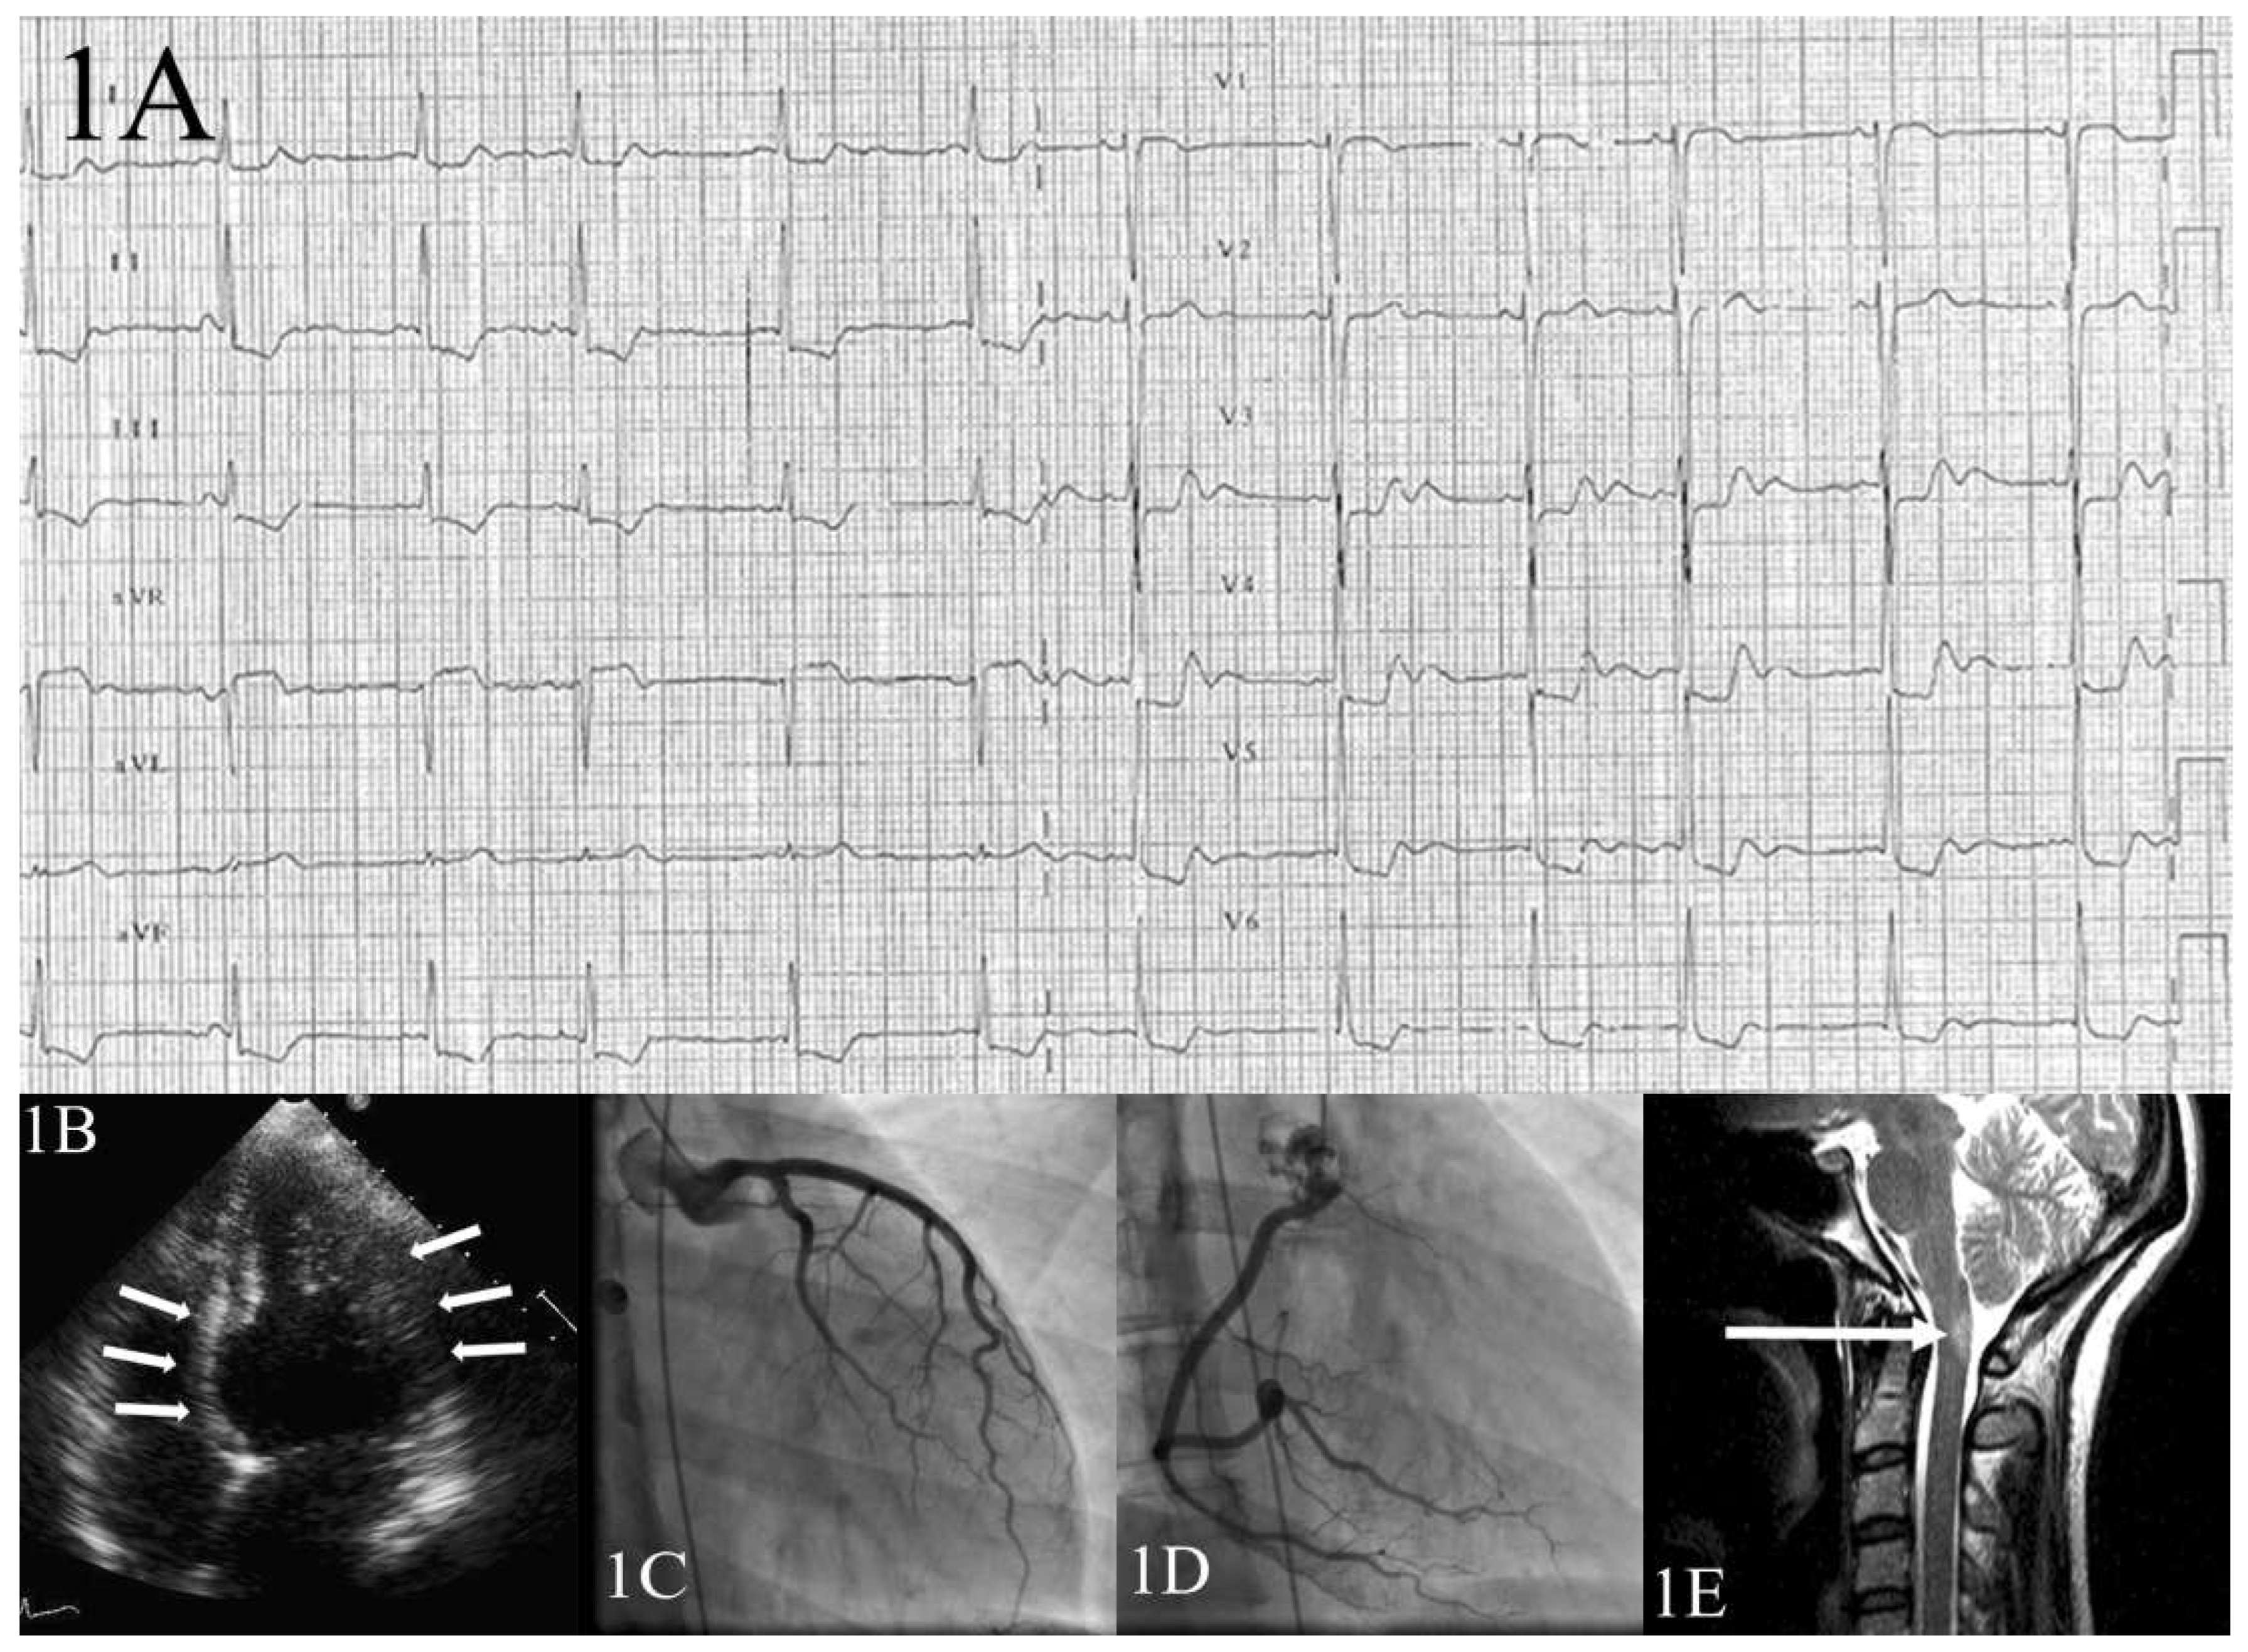

The current report describes a 30-year-old Caucasian woman who came to our attention because she presented with a rapidly progressing bilateral proprioceptive ataxia, spinothalamic hypoaesthesia and gait impairment. Two years before, the patient had experienced an analogous neurological episode. Medical history, clinical, laboratory and imaging findings supported the diagnosis of an acute multiple sclerosis relapse according to McDonald criteria. Intravenous, and later oral, steroid therapy was implemented with suboptimal patient relief. Ten days later the patient was transferred to the coronary care unit because of acute typical chest pain. With the exception of ongoing significant neurological impairment no further clinical findings nor haemodynamic compromise were present. The electrocardiogram (ECG) showed diffuse ST-segment depression (Figure 1A), the corrected QT-interval was not prolonged (409 msec) and brain natriuretic peptide (BNP) levels were not measured. Transthoracic echocardiography showed akinetic basal segments (Figure 1B: 4-chamber view, end-systole: arrows) and apical hypercontractility with slightly reduced (45–50%) left ventricle ejection fraction (LVEF%) (see online Video 1: four-chamber view). These findings were inconsistent with a moderate increase in serum troponin (peak 3.5; reference value <0.09). The patient immediately underwent selective coronary angiography, which disclosed the absence of any coronary stenosis or dissection (Figure 1C–D). Although cardiac magnetic resonance imaging (MRI) was not performed, the diagnosis of myocarditis was reasonably rejected owing to the absence of systemic inflammation (normal C-reactive protein, leucocyte and procalcitonin values), negative bacterial blood cultures and viral tests. Phaeochromocytoma was excluded because of normal 24-hour urine fractionated catecholamines and metanephrines. Two days later the ECG showed complete spontaneous normalisation (Figure 2). Thus, the diagnosis of basal (inverted) Tako-Tsubo cardiomyopathy (TTC) was retained.

Cerebrospinal MRI performed 5 days before the TTC episode showed an acute inflammatory lesion affecting dorsal medulla (Figure 1E). This area is involved in cardiovascular homeostasis and regulation of autonomic responses to stressful events through sympathetic drive [1], thus providing a hypothetical pathological substrate for this TTC episode. This medullary lesion recovered at 5-month MRI follow-up.

Figure 1. Acute phase ECG shows diffuse ST-segment depression. (A) Transthoracic echocardiography, 4-chamber view, end-systole (B) shows akinetic basal segments (arrows) and apical hypercontractility (see also online Video 1). Selective left (C) and right (D) coronary artery angiography show absence of any coronary stenosis or dissection. (E) Axial T2-weighted MRI showing an acute dorsal medullary inflammatory lesion affecting the solitary tract and the ventro-lateral medulla (arrow).